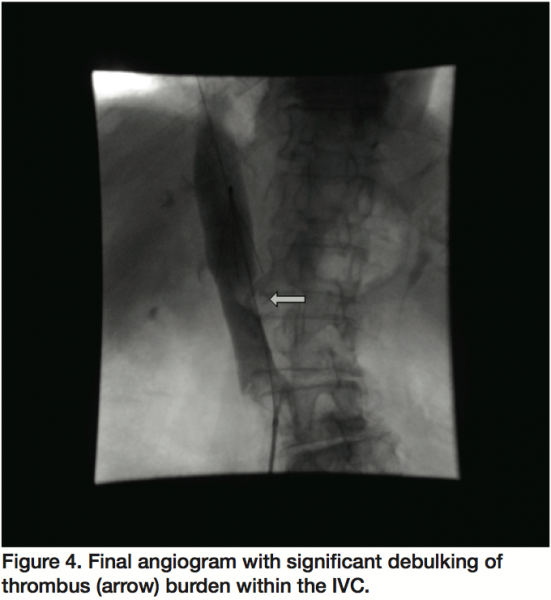

Preceding IVC filter placement, a venogram showed a large filling defect, consistent with a large thrombus, primarily adherent to the medial aspect of the IVC at the origin of the left renal vein (Figure 1). The superior portion of the thrombus had a mobile appearance which was concerning for impending rupture and embolization. A retrievable IVC filter (Celect, Cook Medical, Bloomington, Indiana) was successfully placed between the thrombus and the IVC-right atrial junction (Figure 2). Subsequent to IVC filter deployment, rheolytic thrombectomy (AngioJet, Medrad, Inc., Minneapolis, Minnesota) was performed with 5 consecutive passes within the IVC with significant reduction of thrombotic burden (Figure 3). Final venogram showed a very small residual adherent thrombus without evidence of a mobile component (Figure 4). The patient eventually underwent colonoscopy, which divulged stage 1 colon cancer involving the cecum and consequently, underwent successful partial colectomy with an uncomplicated recovery.